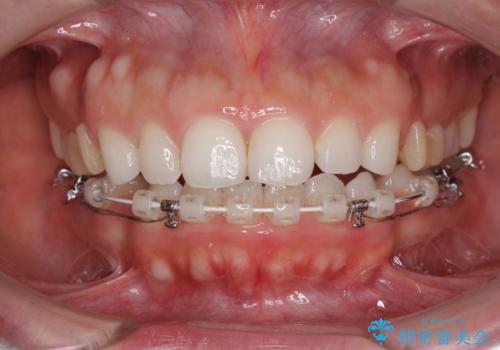

目立たない装置で横顔のシルエットを改善 ハーフリンガルでの抜歯矯正

- 矯正装置

- ハーフリンガル

- 口元の突出感を気にして来院された患者様です。

上下左右の第一小臼歯4本を抜歯して口元を下げる治療計画としました。